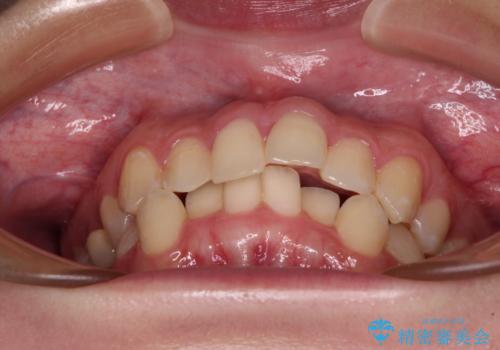

前歯のクロスバイト ギラギラのワイヤー装置で矯正治療

- 前歯のクロスバイトを改善したいとのことで来院された患者様です。

マウスピース矯正では前歯の神経への負担が大きいことを懸念され、ワイヤー装置による矯正治療を行うこととしました。

クロスバイトが改善する際は、前歯しか接触しないため、痛みがあったり食事が取りにくかったりと、不便な時期がありますが、1年強の短期間で無事に治療を終えることができました。